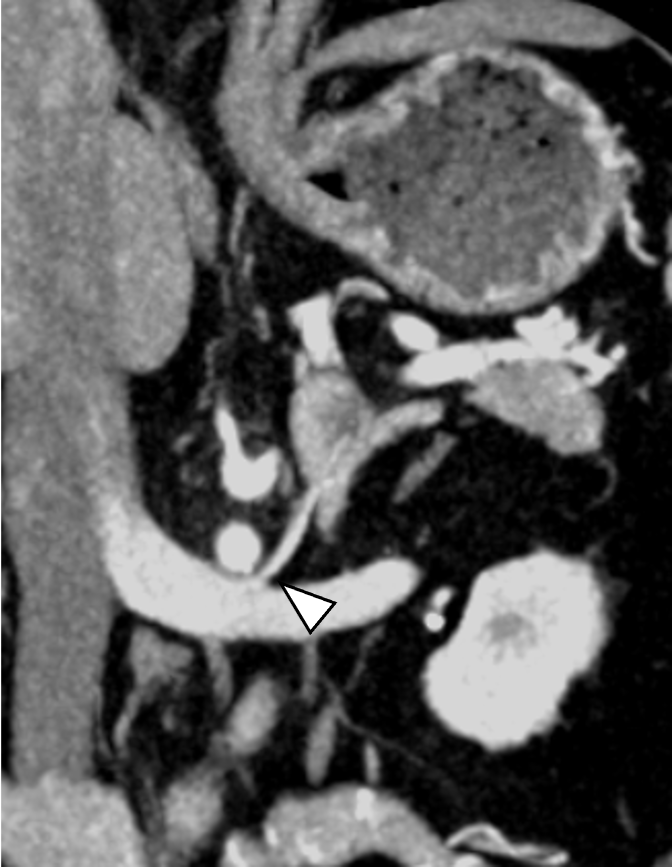

当該疾患の診断における造影CTの役割

原発性アルドステロン症は, 治癒可能な二次性高血圧であり, 本態性高血圧より脳・心血管, 腎合併症の頻度が高く, その診断および治療の重要性が指摘されている, 片側性のアルドステロン症の場合, 外科的切除によりアルドステロン過剰の正常化, 高血圧および臓器障害の改善・防止が期待できる, このため, 手術が考慮される場合には副腎静脈サンプリングによる機能的局在診断を行う, 原発性アルドステロン症診療ガイドライン20211)では, この副腎静脈サンプリングの成功率を向上させる方法の一つとして, ダイナミックmulti-detector row CT(MDCT)が推奨されている, MDCTでは, 横断像やMPR(Multi planar Reconstruction)を用いて, 副腎静脈の走行やvariationの確認などを行うが, これに加え当院では,仮想透視画像を作成し, 右副腎静脈の下大静脈開口部のレベルや, 副肝静脈との位置関係など, 立体的な解剖学的把握を行っている, その結果, サンプリング時に, スムーズかつ的確なカテーテル操作が可能となる.

本検査における後期動脈相は, 右副腎静脈と下大静脈との合流部, また左副腎静脈と下横隔静脈, 腎静脈との合流部の形態評価が求められる重要な撮影時相である. そのため30sec注入時間固定法とbolus tracking法の併用を行い, 腹部下行大動脈において+100HUのCT値上昇をトリガーとし, 20secのdelay timeにて後期動脈相の撮影を行っている. その後の門脈優位相は, トリガーから40secの撮影とし, 主に副肝静脈と下大静脈との合流部の形態評価が目的とされる. 造影コントラスト向上のため. 可能な限り低管電圧撮影が行えるよう留意している. なお, 本症例は, 造影剤量がプロトコルより少ない症例であったが, 低管電圧撮影や後期動脈相の最適な撮影タイミングにより, 副腎静脈を良好に描出し得た.